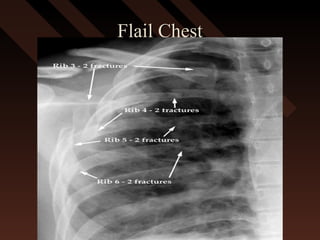

Flail ChestFlail Chest

The breaking of 2The breaking of 2

or more ribs in 2or more ribs in 2

or more placesor more places

S/S of Flail ChestS/S of Flail Chest

 Shortness of BreathShortness of Breath

 Paradoxical MovementParadoxical Movement

 Bruising/SwellingBruising/Swelling

 Maybe associated with hemothorax,Maybe associated with hemothorax,

pneumothorax.pneumothorax.